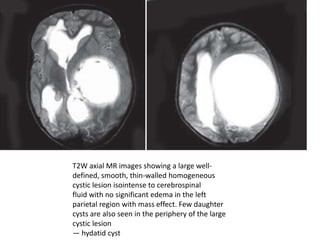

T2W axial MR images showing a large well-

defined, smooth, thin-walled homogeneous

cystic lesion isointense to cerebrospinal

fluid with no significant edema in the left

parietal region with mass effect. Few daughter

cysts are also seen in the periphery of the large

cystic lesion

— hydatid cyst